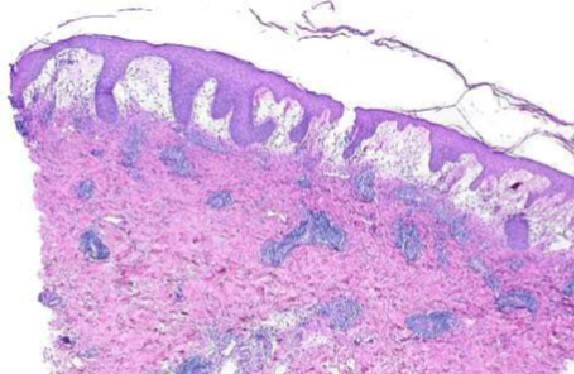

LICHEN SCLEROSUS ET ATROPICUS (LS&A)

Dx?

DDx?